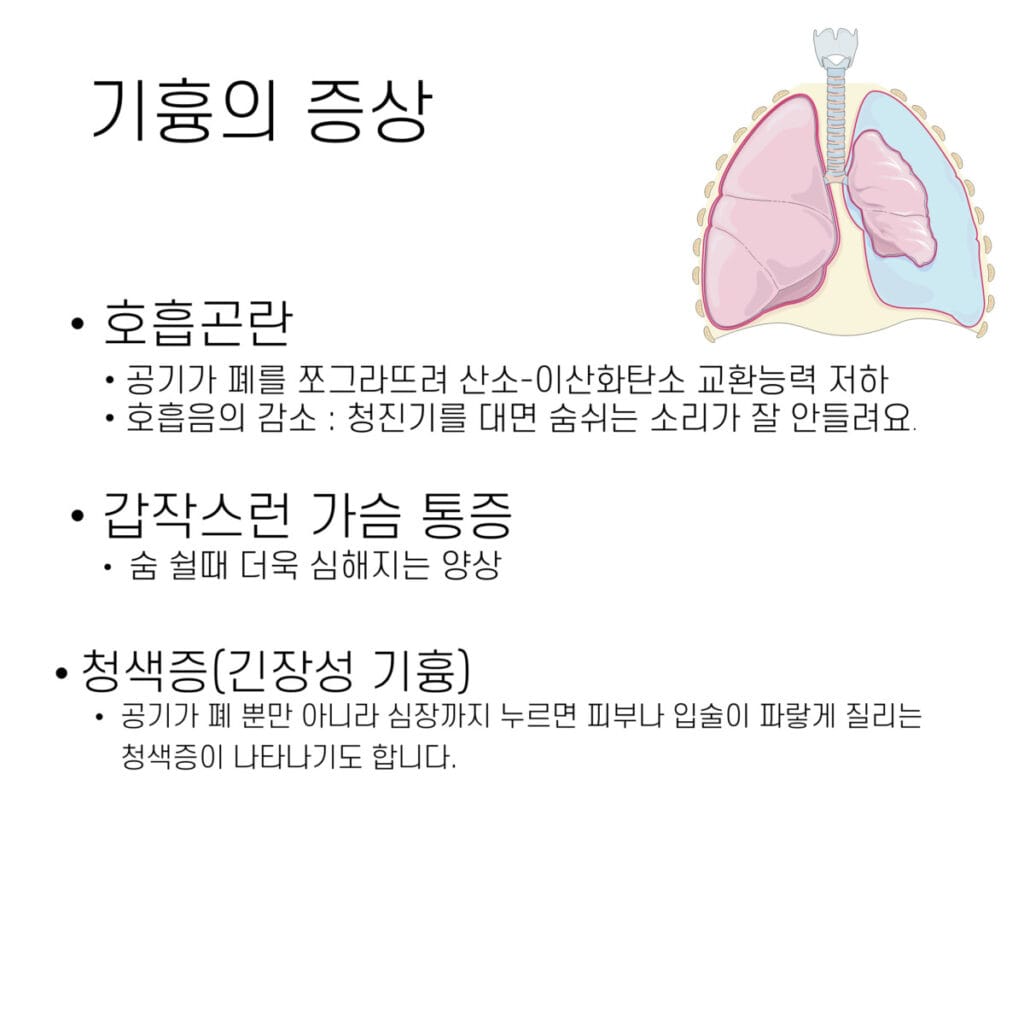

임상양상

갑작스러운 흉통과 호흡곤란이 주요 증상으로 나타납니다.

| 주요 증상 |

| ✅ 갑작스러운 일측성 흉통 및 호흡곤란. |

| ✅ 청진 시 감소된 호흡음(affrication sound 감소). |

| ✅ 긴장성 기흉의 경우 저혈압, 청색증, 경정맥 팽창 동반. |